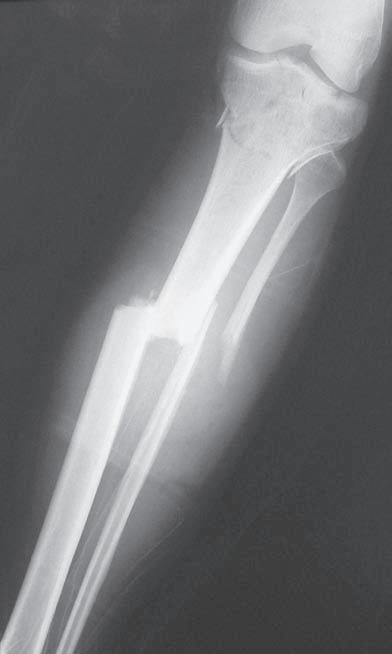

Obr. 2.1 Jednoduchá příčná zlomenina tibie, typ A podle AO klasifikace. Současně je přítomná nedislokovaná nitrokloubní zlomenina proximální části

Obr. 2.2 Spirální zlomenina distální části tibie a šikmá zlomenina zevního kotníku. Typ A podle AO klasifikace

Obr. 2.3 Tříštivá zlomenina diafýzy tibie – hlavní fragmenty, tj. proximální a distální, nejsou v kontaktu. Typ C podle AO klasifikace